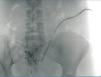

Case 1. 56-year-old; 4 months on CAPD without issues. Episode of severe peritonitis due to an anaerobic bacterial infection. Once recovered, the patient was started on APD. After several weeks, the patient complains of not being able to sleep due to multiple alarms. The treatment regime is evaluated, and a major drainage difficulty is revealed. A simple abdominal x-ray reveals no important findings; the tip of the catheter is observed in the pelvis. A catheterography is administered, which reveals a large loop in the catheter. The situation is resolved through the use of a guide and increased laxative treatment (Figure 1).

Figure 1. Case 1